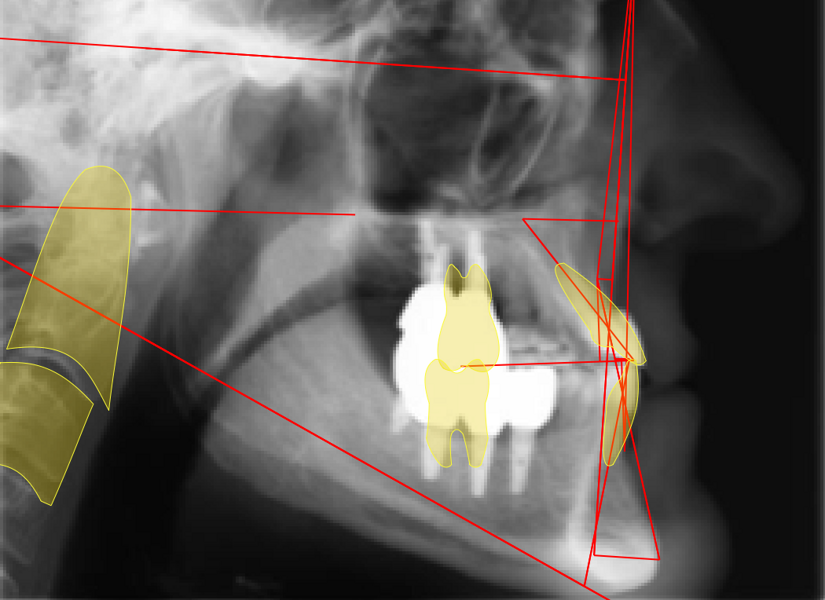

Tongue posture alteration, atypical swallowing and perioral muscle dysfunction from birth result in the development of jaw and dental dysmorphism. The masticatory muscles then reinforce functional alteration. Once altered during development, the oral cavity grows, matures and ages, progressively worsening the peculiar and groupable morphotypes (Figs. 1–5).

Static characteristics described by Mew are useful for classifying physiological and pathological morphology of development in children, as well as for anticipating or explaining altered evolution in adult patients (Fig. 6).15 Dynamic characteristics to be considered are the following:

Fig. 6: Mew classification based on tongue positioning.15

This patient, like all patients requiring interdisciplinary rehabilitation, had to first undergo periodontal treatment and caries restoration (Fig. 17). At the same time, it was important to rehabilitate swallowing with Froggymouth and relax the masticatory muscles and relieve the TMJs with an occlusal device. We could then study the orthodontic treatment plan using Invisalign ClinCheck (Align Technology) and showed the treatment plan to the interdisciplinary team and to the patient (Fig. 18). We were then able to create the correct sequence of orthodontic treatment, bone augmentation and implant surgery needed for the posterior edentulous spaces.